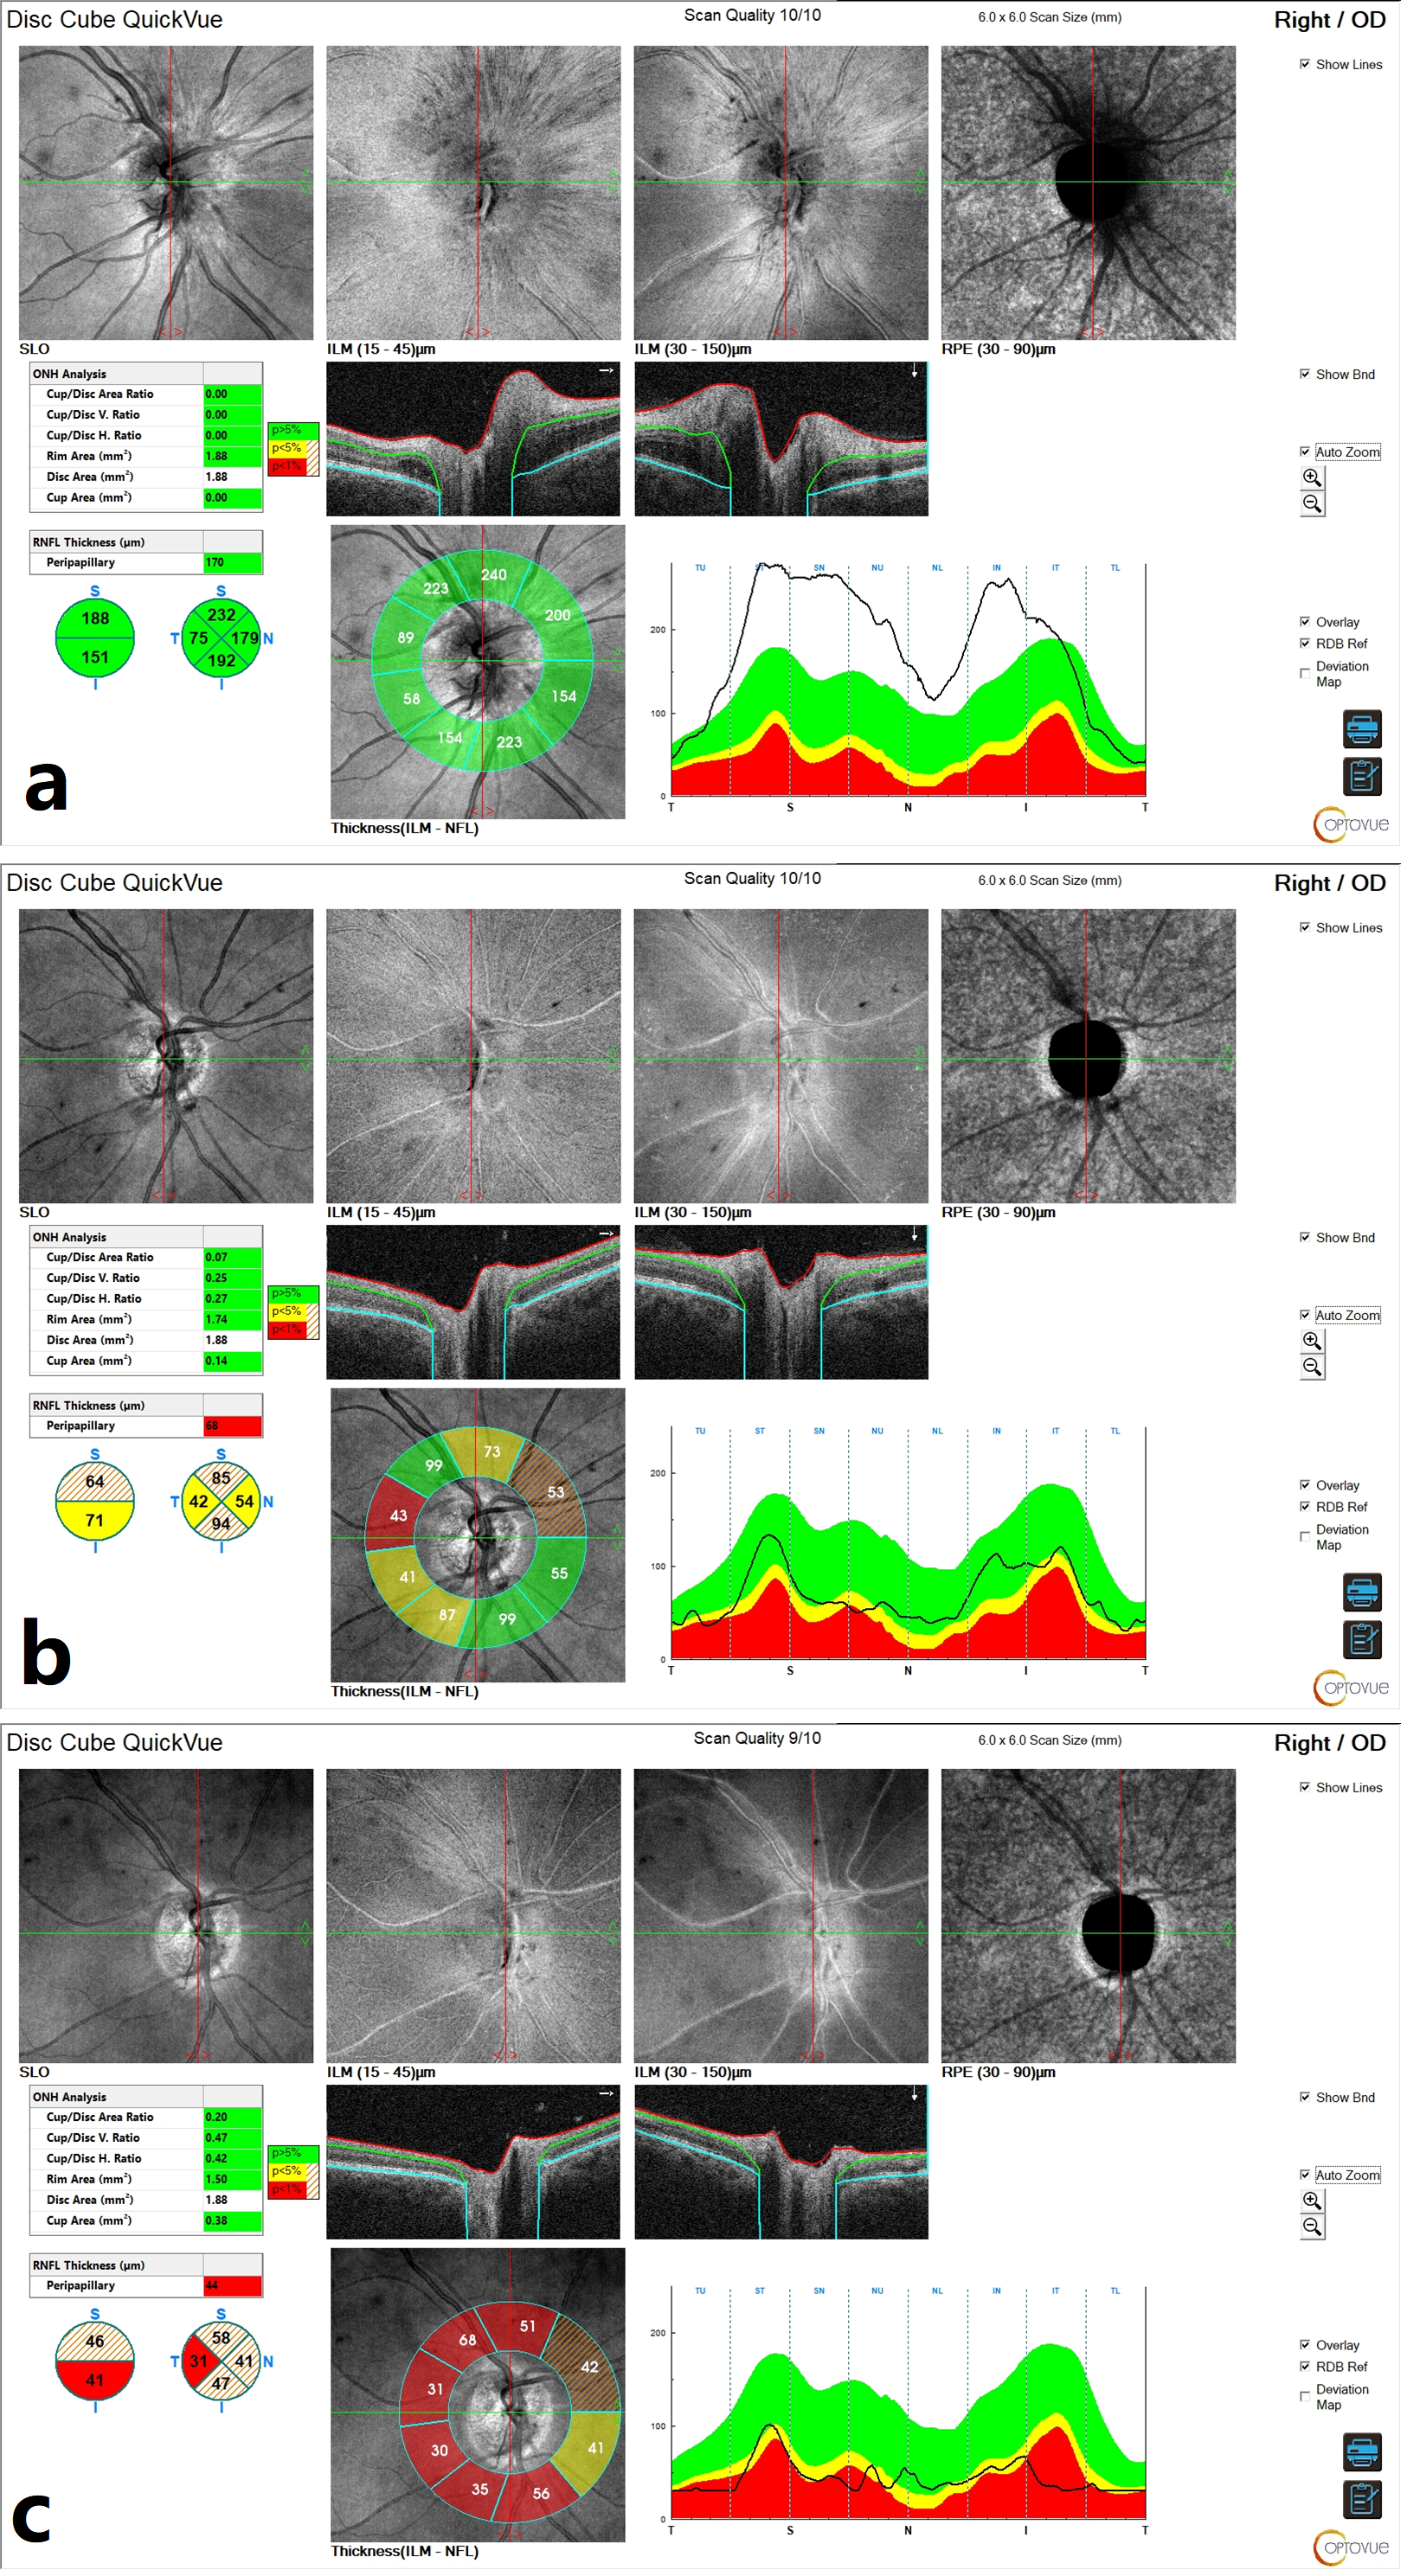

Initial optical coherence tomography (OCT) of the right ONH demonstrated an elevation of the retinal nerve fibre layer (RNFL), consistent with ONH edema (

Figure 2a). Macular OCT revealed no abnormalities.

Figure 3c), while OCT scans of the ONH showed progressive RNFL thinning, suggestive of optic nerve fibre atrophy during follow-up (

Figure 2b,c). The left eye remained unaffected throughout the course of the illness (